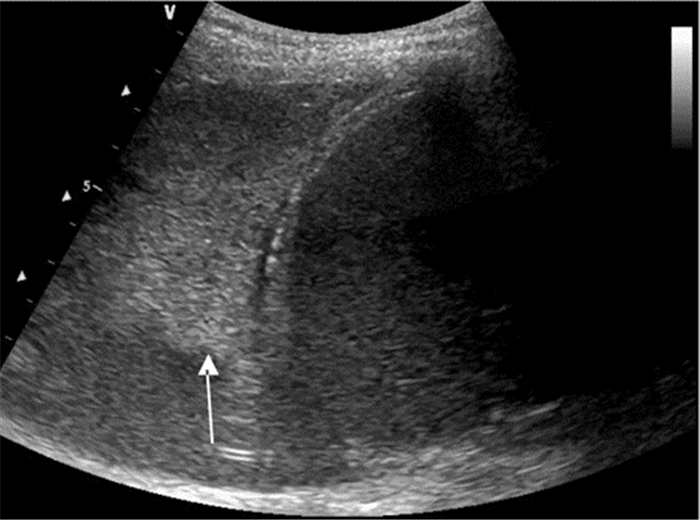

将探头置于目标肋间隙,于胸壁软组织下可见一条随呼吸滑动的高回声线,即为胸膜线,其后可见与之平行、等距、回声强度不断衰减的多条线——A线(图 8)。胸膜线随呼吸往复运动的图像称为“肺滑动”,M型超声表现为肋骨下方0.5 cm随呼吸向探头方向往复运动的高回声线,即“沙滩征”。部分正常人膈肌上方最后一肋间隙可探及少于3条发自胸膜线、垂直延伸至屏幕边缘而不发生衰减、随呼吸往复运动的激光束样图像——B线(图 9)。

| 图 8 正常肺部超声征象:左图横向箭头所示为A线,其与胸膜平行等间距逐渐减弱。右图为M超下“沙滩征” |